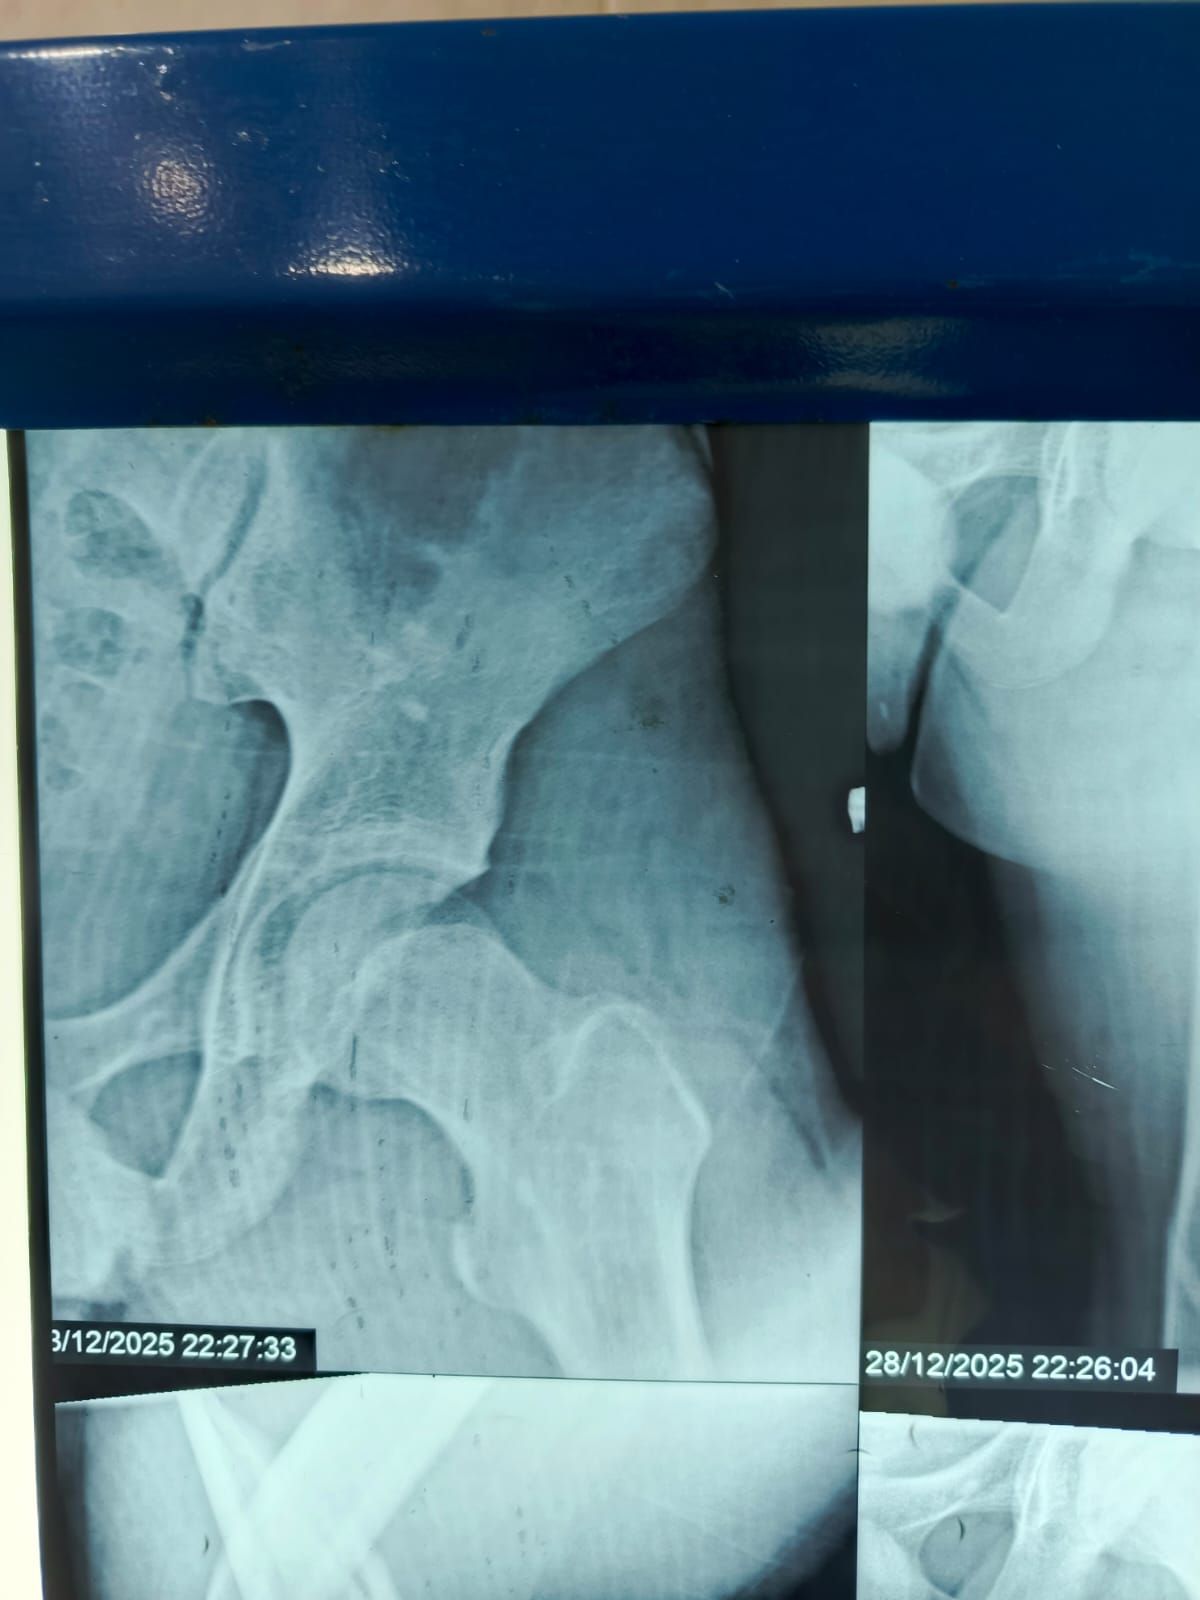

نجح الفريق الطبي بقسم الطوارئ والعمليات بمستشفى مغاغة العام بمحافظة المنيا ، في إنقاذ شاب يبلغ من العمر 16 عامًا، تعرض لحادث مروري مروع أسفر عن كسر مفتت متعدد المواضع بعظمة الفخذ الأيسر، وذلك من خلال إجراء جراحة متقدمة باستخدام تقنية المسمار النخاعي التشابكي في زمن قياسي.

وفور وصول المصاب إلى قسم الطوارئ، جرى التعامل الفوري معه، وتم اتخاذ القرار الطبي العاجل بإجراء جراحة المسمار النخاعي التشابكي دون فتح موضع الكسر، بما يتوافق مع أحدث البروتوكولات الطبية العالمية. واستغرقت العملية نحو ساعتين ونصف فقط، غادر بعدها المريض غرفة العمليات في حالة مستقرة.

وتميزت الجراحة بعدة مزايا، من بينها : جروح جراحية محدودة للغاية ، وتقليل فرص النزيف والعدوى إلى أدنى حد ، وتسريع معدلات التئام العظام مقارنة بالطرق التقليدية.